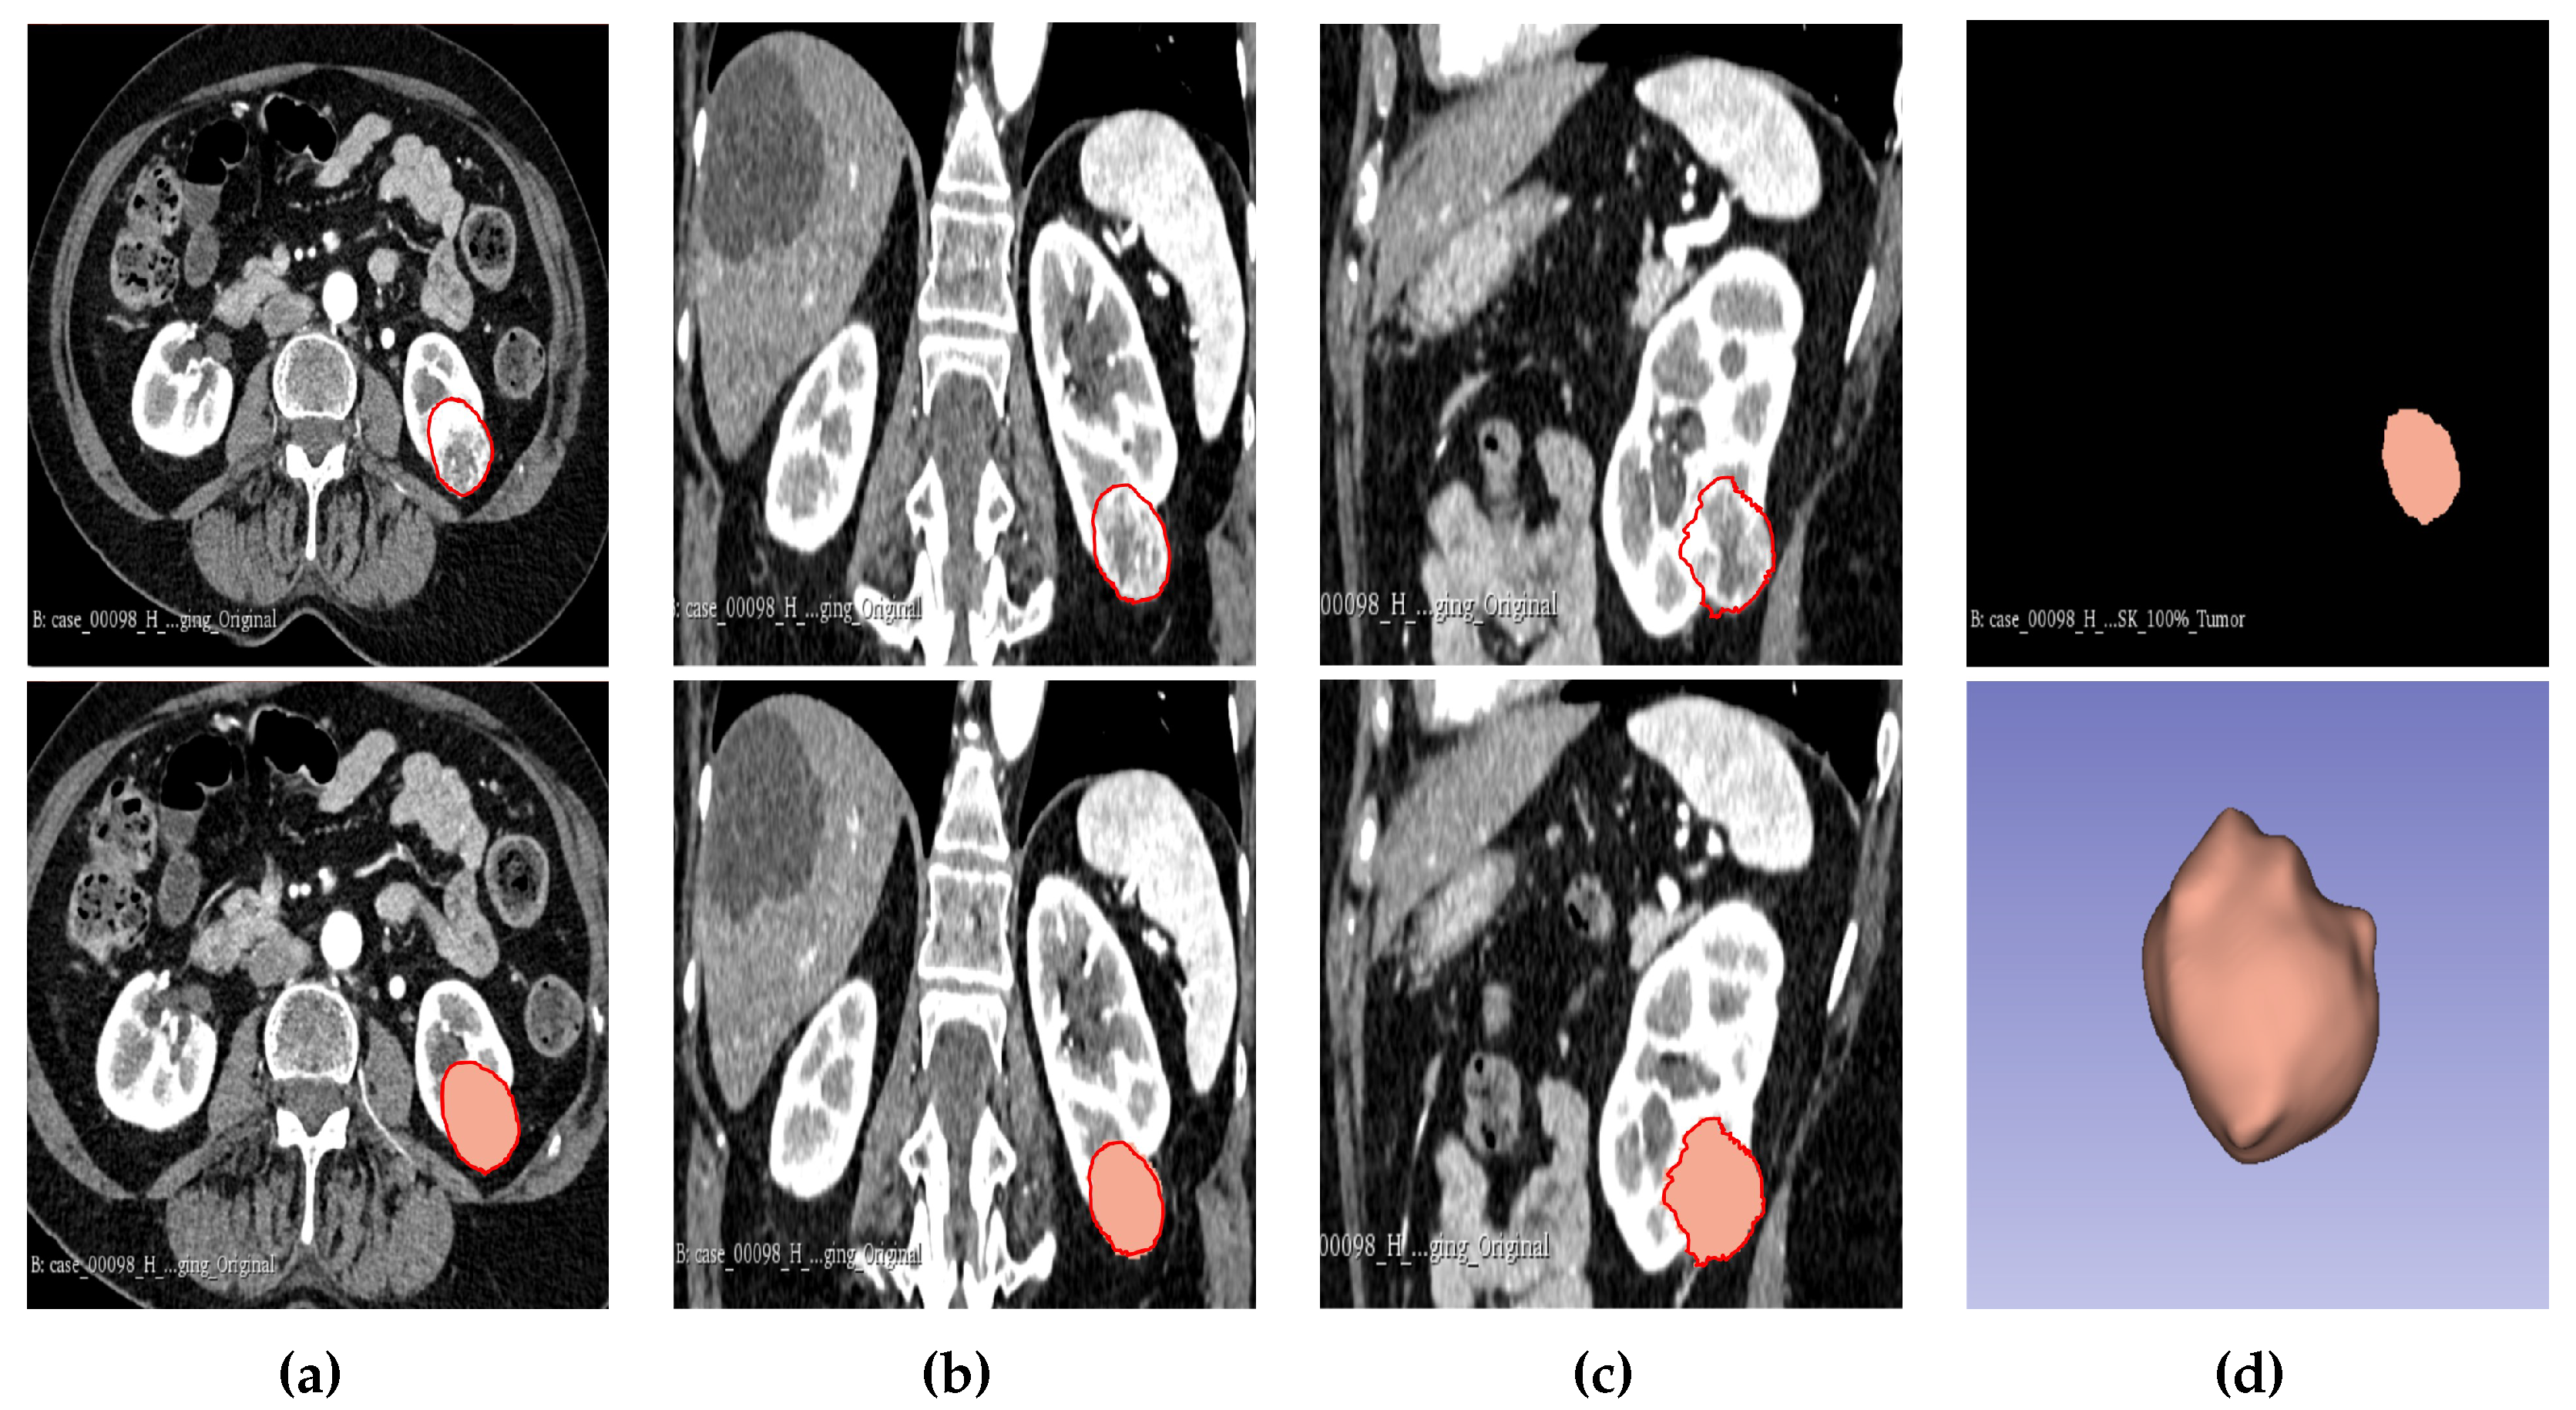

2.5. Tumour Sub-volume Segmentation Technique